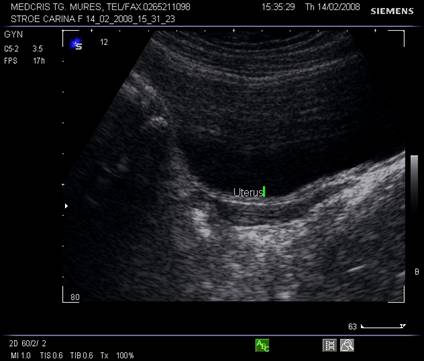

Fig. Nr.358. Uter in sectiune longitudinala, in anteversoflexie

Fig. Nr.359. Sectiune transversala la ecografia transvaginala, la nivelul corpului uterin